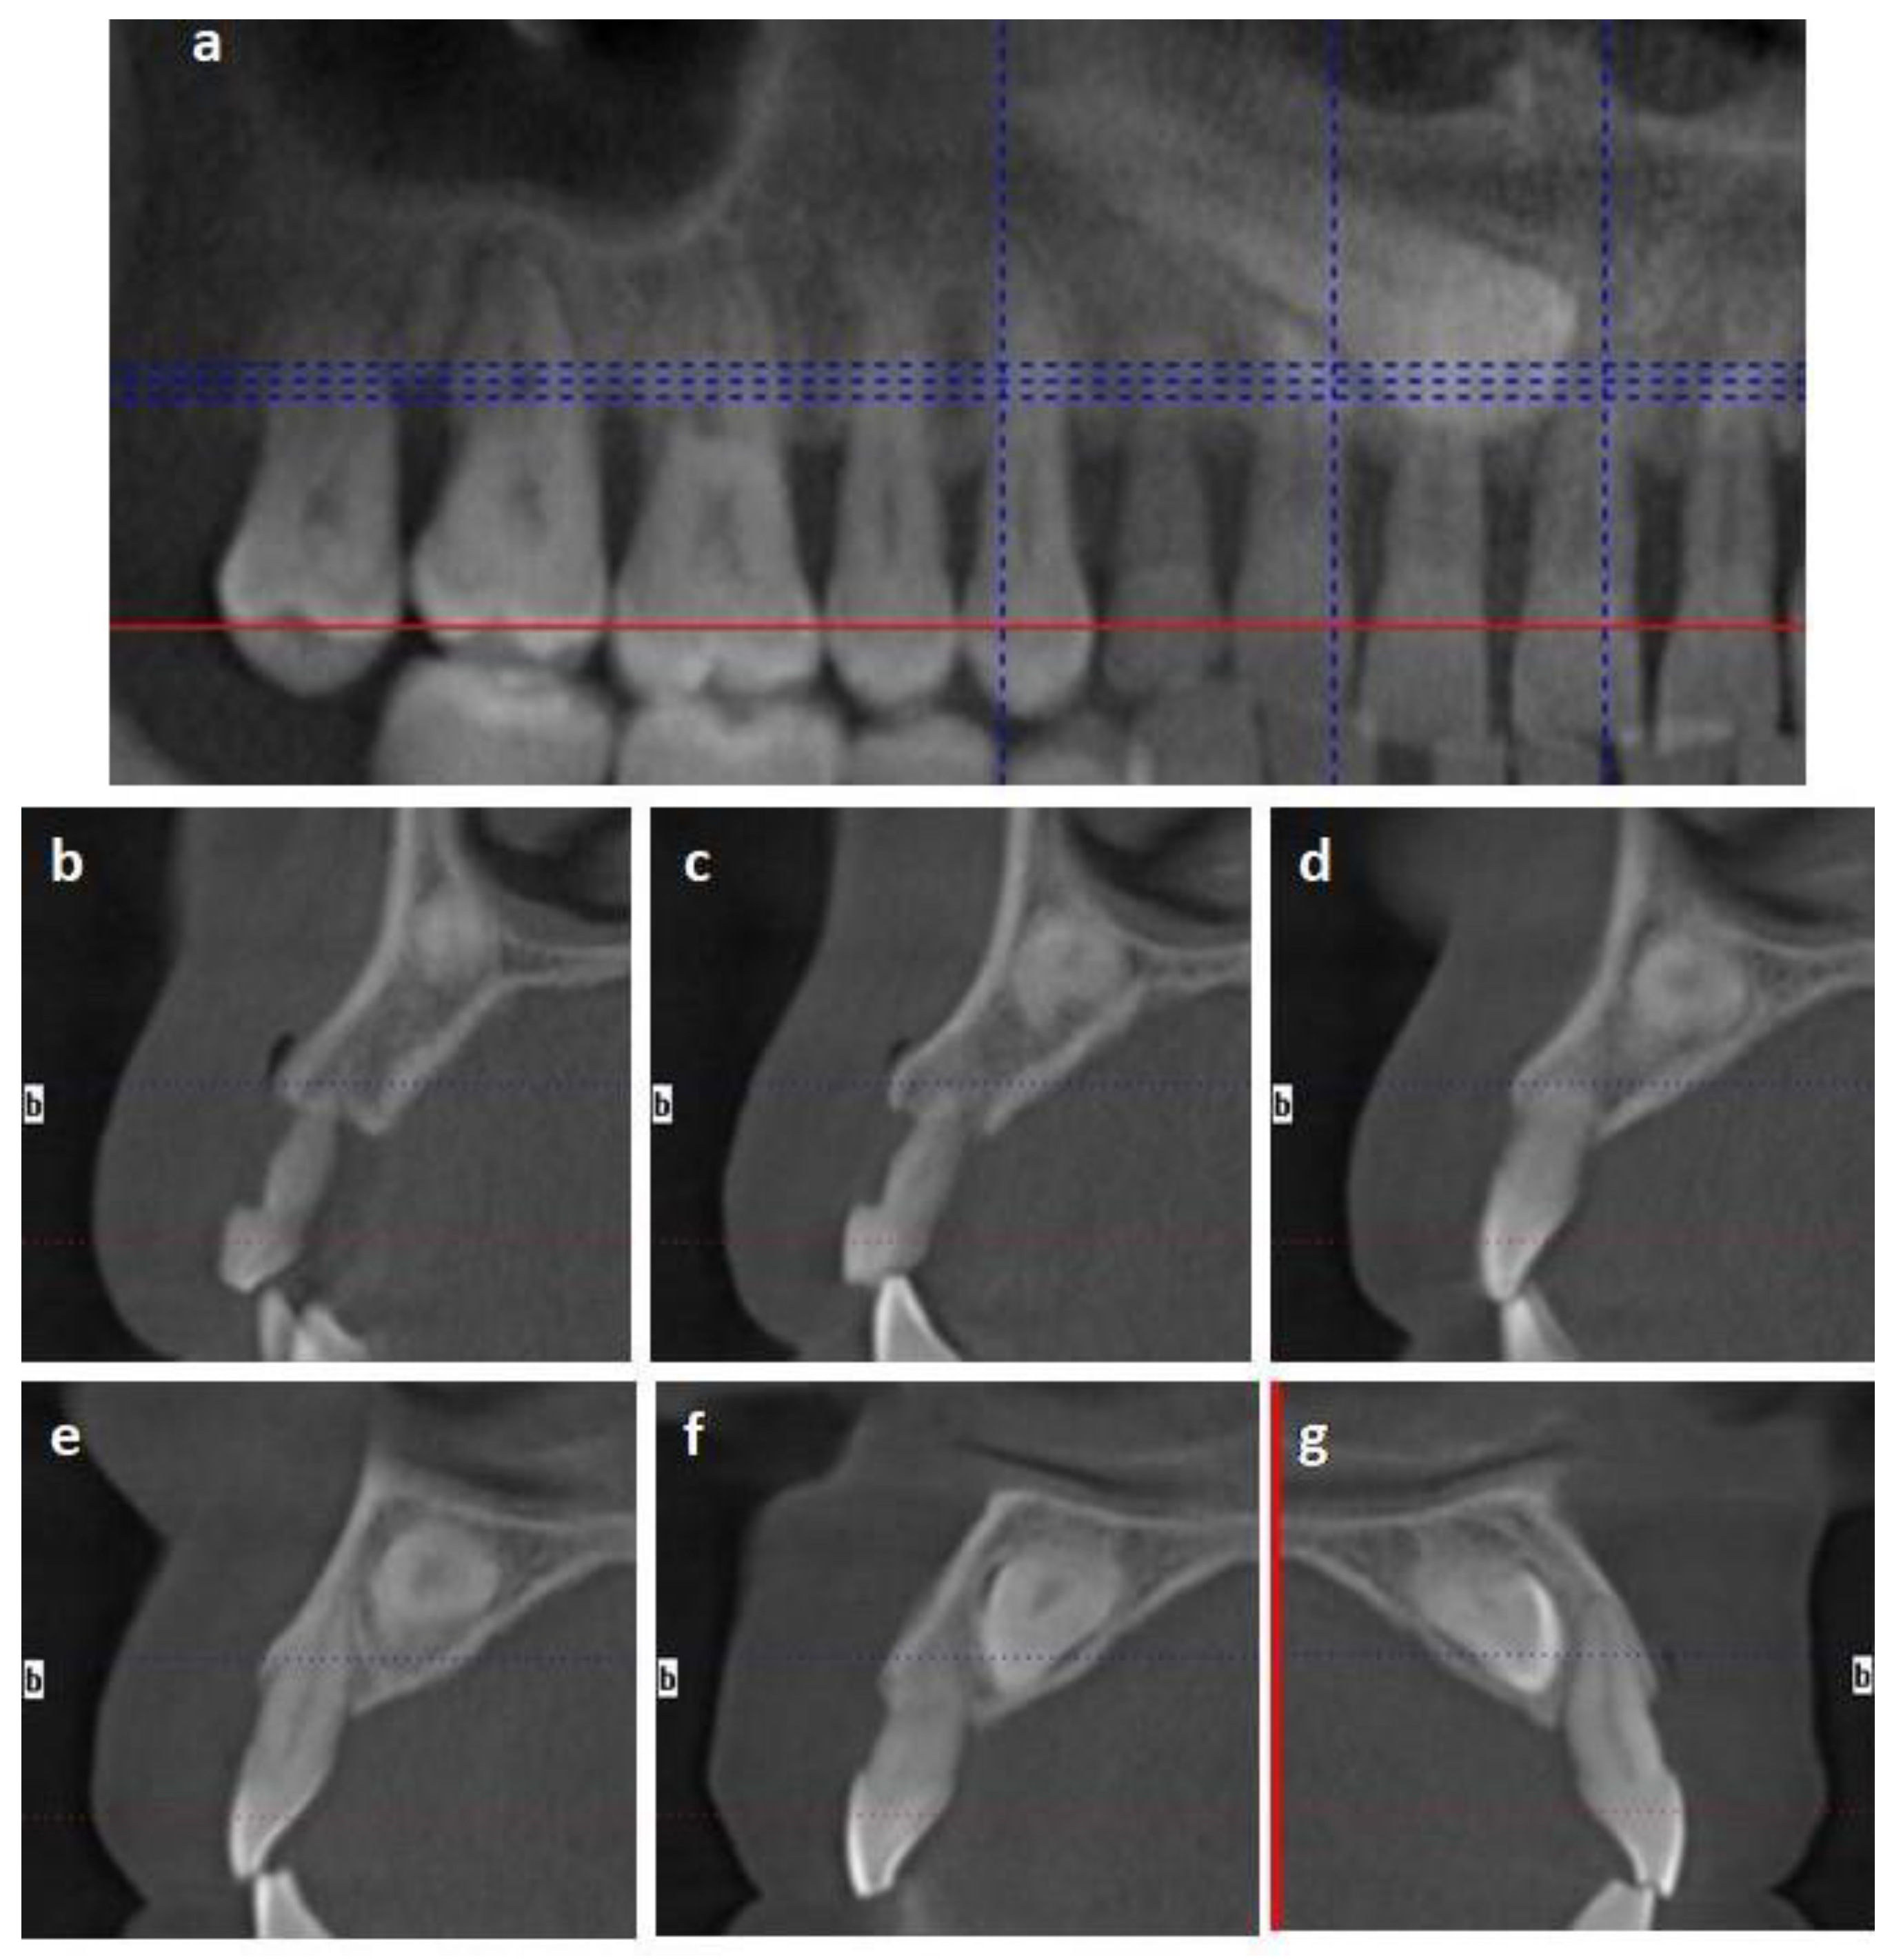

2.1.1. Case 1

2.1.2. Case 2

2.2.1. Case 1

2.2.2. Case 2